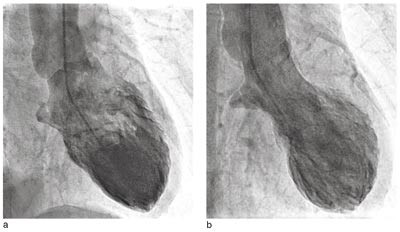

Pasient 2. 53 år gammel kvinne, som de siste to måneder før det aktuelle hadde vært plaget med erosiv, seropositiv revmatoid artritt i venstre hånd. Ellers hadde hun stort sett vært frisk. I forbindelse med en ferietur ble hun innlagt i sykehus i Polen grunnet sentrale brystsmerter og dyspné. Ved klinisk undersøkelse var det ingen vesentlige patologiske funn, bortsett fra lette sibili over lungene. Arterielt blodtrykk var 135/80 mm Hg, pulsfrekvens 80 per minutt. Klinisk og røntgenologisk var det mistanke om pneumoni, og hun fikk behandling med penicillin. EKG viste tydelig inversjon av T-takken i avledningene I. II, III, AVL og AVF samt V₃ – V₆. Ekkokardiografi viste akinesi av apeks og apikale segmenter av venstre ventrikkel. Det ble fire dager etter innleggelse utført koronar angiografi med ventrikulografi av venstre ventrikkel (fig 1). Man fant helt normale koronararterier. Venstre ventrikkel viste imidlertid akinesi i apikale segment og apikale deler av nedre og fremre vegg, det samme som ved ekkokardiografi. Laboratorieprøvene viste en stigning av troponin I til maksimalt 0,15 ng/100 ml (fra 0,03 ng/100 ml), for øvrig var det upåfallende blodprøveresultater.

I rapporter fra Japan er det beskrevet et klinisk syndrom som imiterer akutt hjerteinfarkt, men som ved nærmere undersøkelser viser transitorisk apikal ballonering av venstre ventrikkel, uten koronarstenoser av betydning (1, 2). Først nylig er det kommet rapporter om tilstanden også utenfor Japan (3, 5). Foruten reversibel patologisk veggbevegelse av apikale segmenter av venstre ventrikkel (fig 1) består dette syndromet av forbigående EKG-forandringer (fig 2) og torakale symptomer. Det foreligger ingen epikardiale koronarstenoser av betydning eller vasospasme, og det er beskjeden stigning i hjerteinfarktmarkører. Ofte utløses tilstanden av emosjonelt eller fysisk stress, men også kirurgiske inngrep, traumer og infeksjoner kan være utløsende årsaker (3, 6, 7).